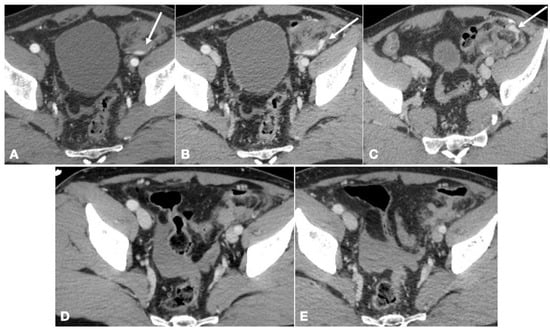

- Trinci, M.; Cirimele, V.; Cozzi, D.; Galluzzo, M.; Miele, V. Diagnostic accuracy of pneumo-CT-cystography in the detection of bladder rupture in patients with blunt pelvic trauma. La Radiol. Med. 2020, 125, 907–917. [Google Scholar] [CrossRef]

- Iacobellis, F.; Ierardi, A.M.; Mazzei, M.A.; Biasina, A.M.; Carrafiello, G.; Nicola, R.; Scaglione, M. Dual-phase CT for the assessment of acute vascular injuries in high-energy blunt trauma: The imaging findings and management implications. Br. J. Radiol. 2016, 89, 20150952. [Google Scholar] [CrossRef]

- Iacobellis, F.; Laccetti, E.; Tamburrini, S.; Altiero, M.; Iaselli, F.; Di Serafino, M.; Gagliardi, N.; Danzi, R.; Rengo, A.; Romano, L.; et al. Role of multidetector computed tomography in the assessment of pancreatic injuries after blunt trauma: A multicenter experience. Gland Surg. 2019, 8, 184–196. [Google Scholar] [CrossRef]